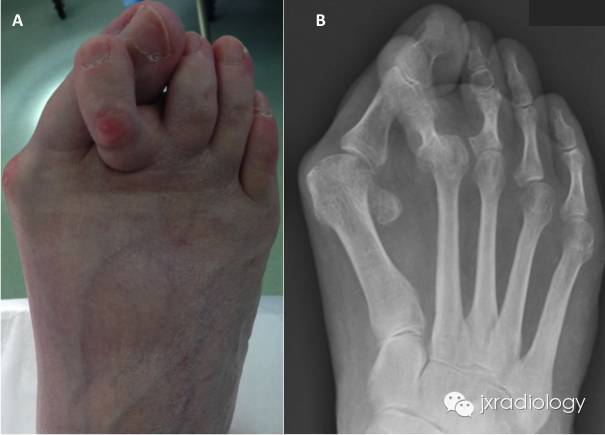

是足部常见疾病,通常双侧发病,随着年龄增加,踇外翻患病率有增加趋势,65岁老年人患病率为12% ~56%,女性多发, 男∶女为 1∶15 ~ 1∶19value币。踇外翻的发生发展与先天性因素和后天性因素具有密切的相关性,其中遗传因素最为明确,调查显示50% ~90%的患者有家族遗传史,为常染色体显性遗传。

当穿较窄或表面较硬的鞋子时,第一跖趾关节内侧会受到挤压和摩擦,形成踇囊炎、踇内侧皮神经炎,导致该处红肿、疼痛;重度者穿任何鞋子都会疼痛,不能步行,严重影响患者的生活质量value币。